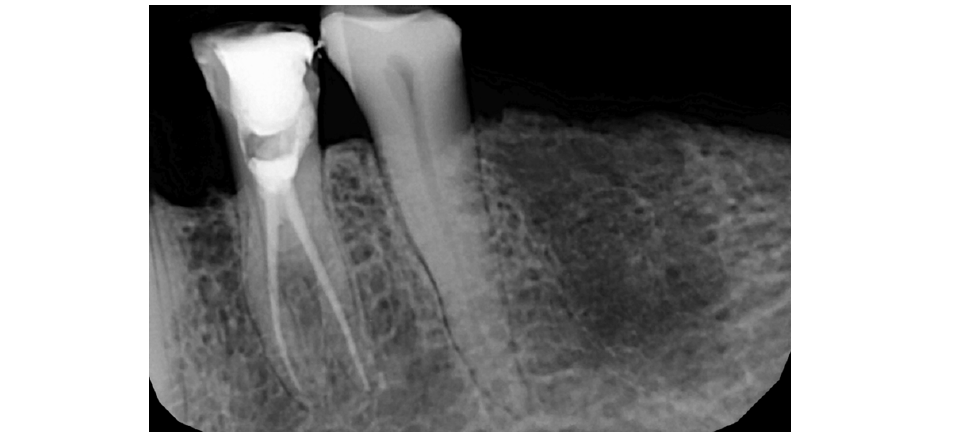

Adequate anaesthesia was achieved with inferior alveolar nerve block. Since the senior citizen had severe gag reflexes the procedure could not be done under rubber dam isolation. The existing cavity preparation was modified, and access cavity was made with round bur; the pulp chamber was entered, and root canal orifices were identified. IOPAR was taken after the initial filing with size 15K-File (Mani, Tochigi, Japan) and found the tooth to have 2 separate roots with 2 different canals of different entry and exit (Figure 2). Working length in each canal was found to be 21 mm. The cleaning and shaping were completed till 6% 25 Hero Shaper files (Micro Mega, Becacon, France). Obturation was done with 6% 25 Master Cone with AH 26 (Dentsply, Germany) as a sealant followed by temporary dressing with Cavit G (3M ESPE, Germany) and postoperative radiograph was taken (Figure 3). Tooth were relieved from occlusion in the functional cusps. The patient was recalled after 5 days for initial review and found to be asymptomatic.

Figure 3:Post-operative radiograph of mandibular left first premolar (tooth #34) following obturation of 2 separate root canals.